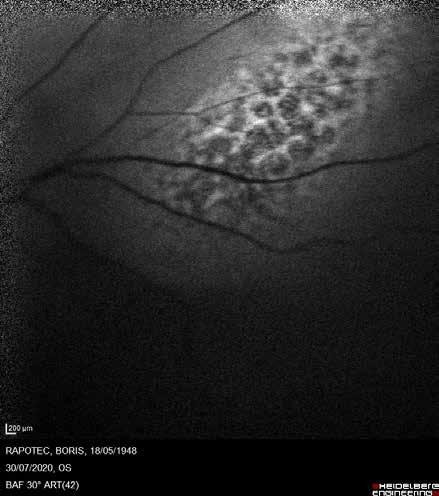

Type 3 MNV refers to the growth of vessels from the retinal circulation toward the outer retina. It is believed that vascular proliferation begins in the deep retinal capillary plexus, with the growth vector extending toward the outer retina. On FA and ICGA, Type 3 MNV appears as a hyperfluorescent intraretinal vascular complex with leakage in the late phases of the examination. Late-phase leakage ion ICGA is a unique feature of MNV lesions. Since these lesions originate from the retinal circulation, they never arise within the foveal avascular zone. Instead, they develop near its edge or at a variable distance from it, typically from the terminal portions of third-order arterioles and venules.5 (Figure 3)

Figure 3. Two examples of Type 3 macular neovascularization. In the first case, Indocyanine green angiography (B) and fluorescein angiography revealing the Type 3 macular neovascularization (arrowhead). Optical coherence tomography (C) showing the detachment of retinal pigment epithelium with the hyperreflective material related to the neovascularization. In the second case, optical coherence tomography (E) showing the intraretinal hyperreflective material related to the neovascularization with intraretinal fluid. Fundus autofluorescence (F) showing abnormalities of retinal pigment epithelium. Optical coherence tomography angiography (G) showing the neovascular lesion.